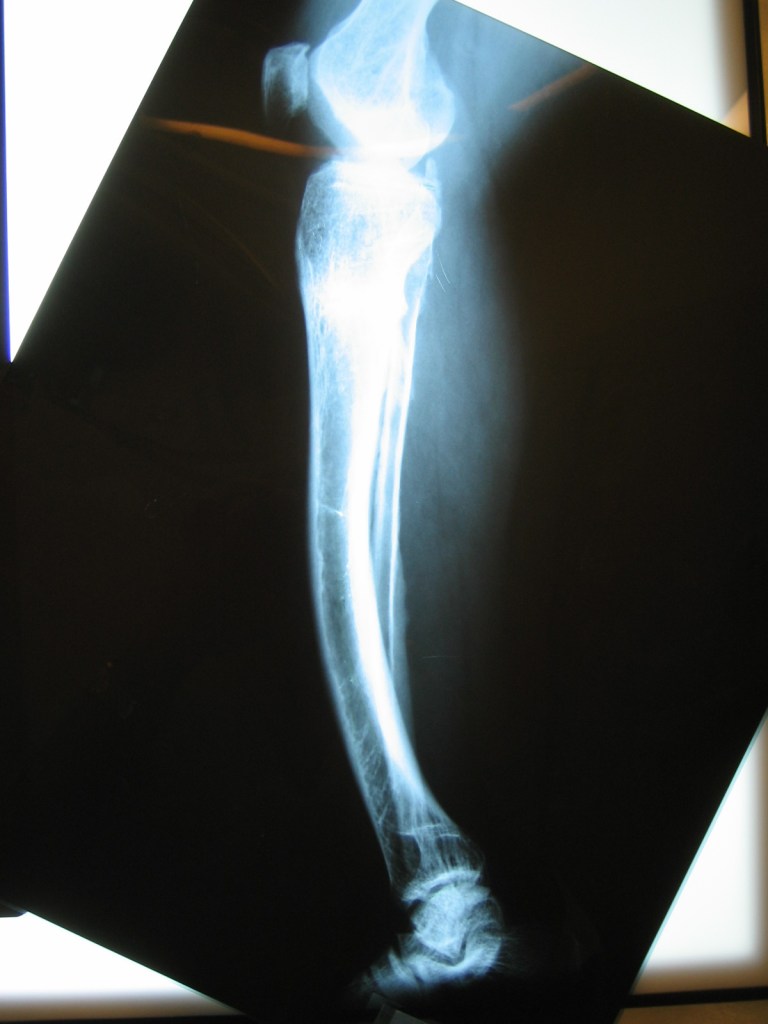

Ferreira nando

niño de 6 años con osmelitis en tibia

Mensaje de Agradecimiento

Luego de una fractura , mi hijo a los 6 años adquirió una infección ósea con exposición del hueso , que no podía tratarse en Chaco, por lo que tras una consulta con el Dr Dratewka , se explico las opciones de tratamiento

Luego de una 1 cirugía que consistió en remover todo el tejido muerto y acortar el hueso , pudimos tratar la infección ,y en una 2 cirugía alargar la pierna nuevamente

Hoy mi hijo ha podido volver a todas sus actividades